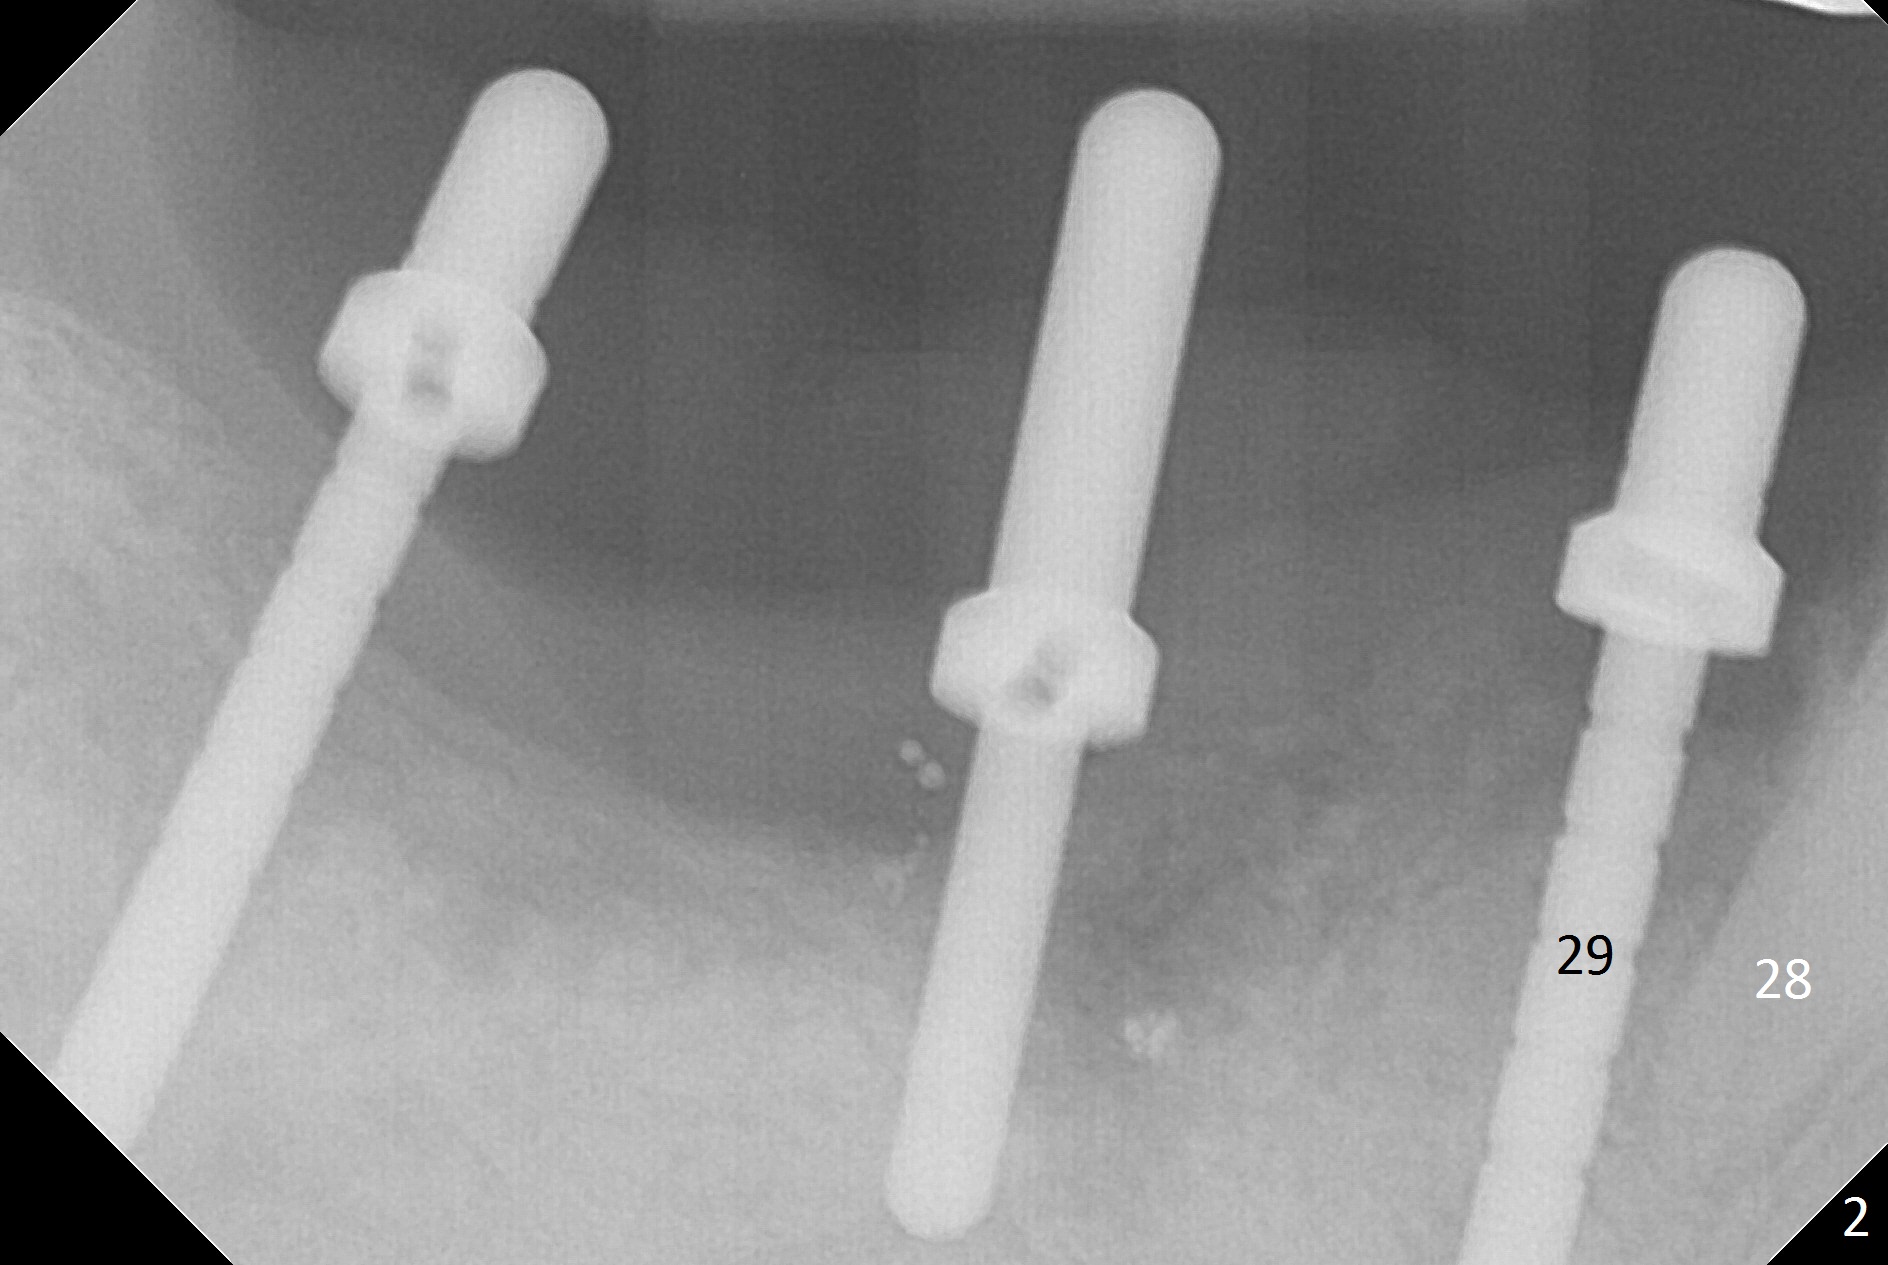

Initial osteotomy at #29-30 shows that there is clearance at #31, but not at #30 (Fig.1 (red dashed line: the superior border of the Inferior Alveolar Canal)) and that the osteotomy at #29 is close to the root of #28 (Fig.2). Moving the osteotomy of #29 distally using Lindamann bur is not sufficient (Fig.4 when a 3.8x10 mm drill is in place). A de novo osteotomy is established distally (Fig.5,6 (red dashed line: old osteotomy)).